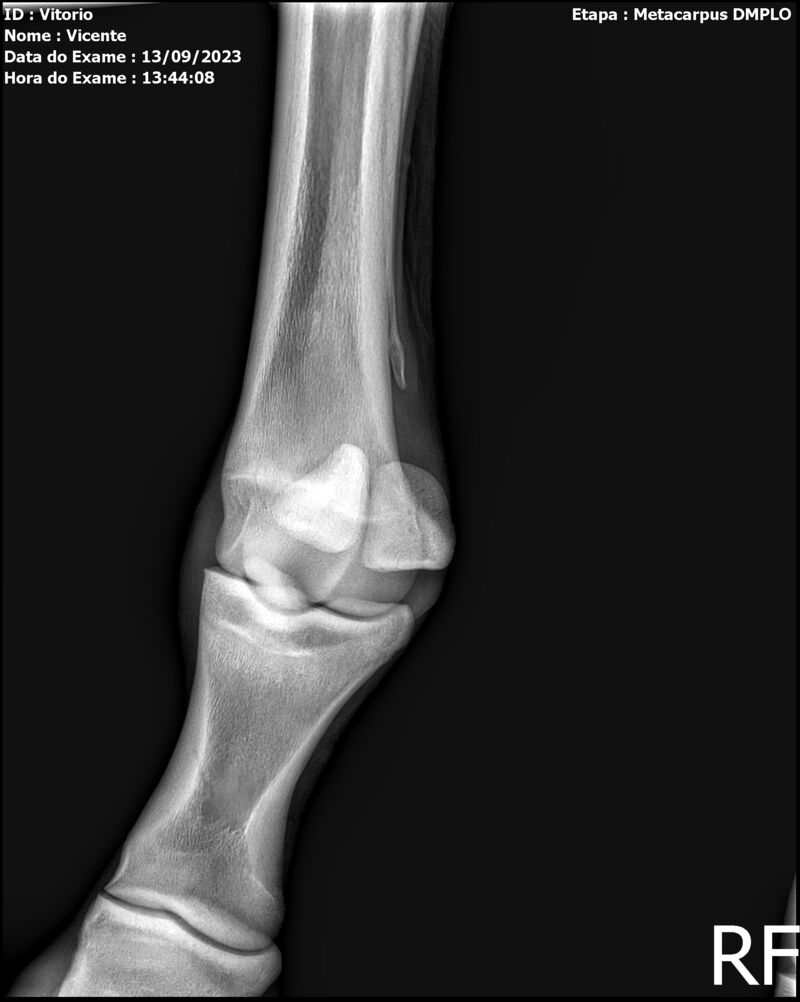

THUNDER ZC

Raça: BRASILEIRO DE HIPISMO

Sexo: MACHO - POTRO

Nascimento: 17/09/2022

Altura Aproximada: 1,54

Pel.: CASTANHO

Registro: EM AND

Vend.: VICENTE CONTE

Local : PORTO FELIZ/SP